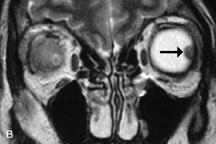

Retinoblastomas display moderate signal intensity on T1-weighted studies and a low signal on T2-weighted images.31,80,85 Calcification can be easily detected by CT and ocular ultrasonography but is not imaged by MRI.25,50 The presence of optic nerve involvement is best evaluated by MRI.